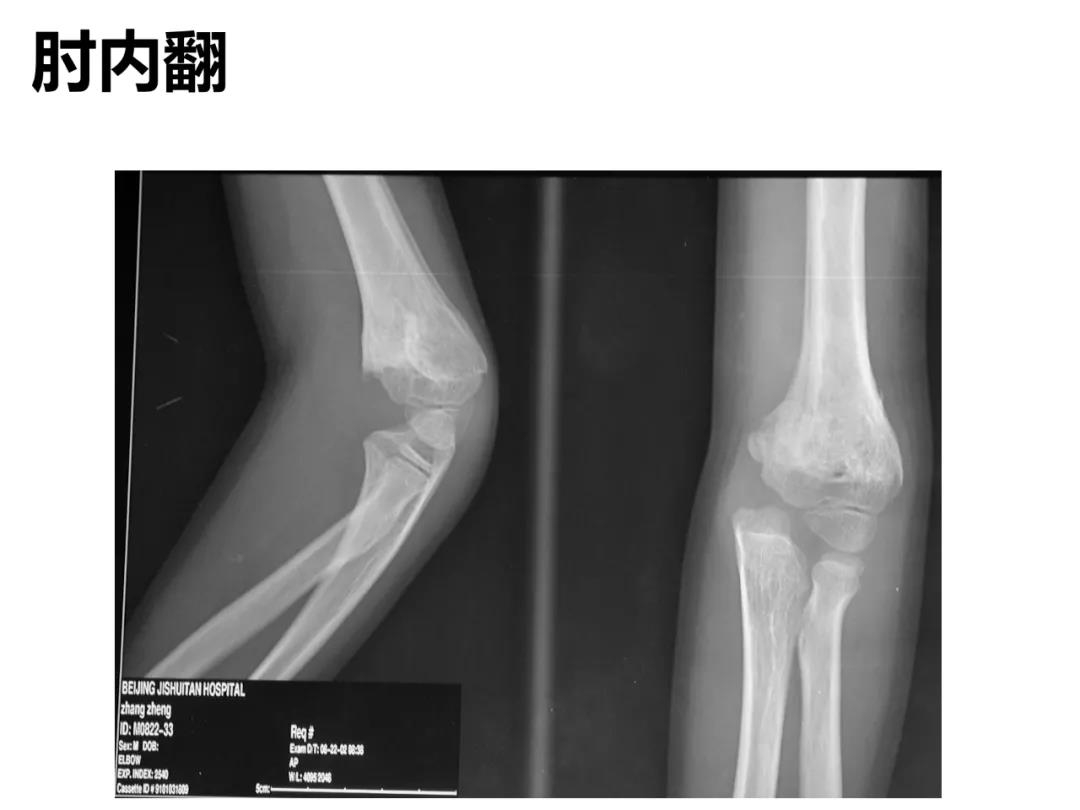

小儿骨科X线片汇总,临床读片宝典!